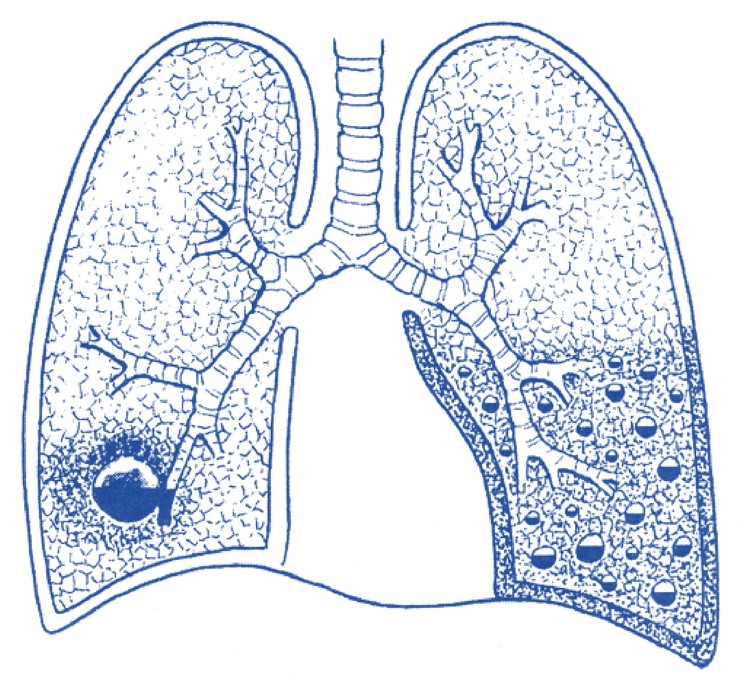

Гематогенно-эмболические

острые гнойные деструкции лёгких встречаются

не более чем в 2-5% случаев. Одним из убедительных доказательств

эмболического происхождения острых гнойно-деструктивных заболеваний

легких является состояние септикопиемии, при которой в легких находят

множественные гнойники. Источником для эмболии могут быть различные

гнойные процессы, но наиболее часто эмболические нагноения возникают

при сепсисе различного происхождения, тромбофлебите, септическом

эндокардите, остеомиелите.

Фрагментации

инфицированных эмболов и заносу их в легкие могут

способствовать оперативные вмешательства на инфицированных тканях. При

тромбировании бактериальными эмболами или частицами ткани из

септического очага концевых ветвей легочной артерии гнойному

расплавлению обычно предшествует инфаркт легкого, который имеет

клиновидную форму с основанием, обращенным к периферии. Это объясняет

характерную для эмболии клиническую картину в виде острого начала,

внезапных болей в боку, кашля с незначительным количеством мокроты и

примесью крови.

Вследствие

наиболее обычной локализации эмбола в периферических

участках легкого, после гнойного расплавления инфаркта очень часто

наступает прорыв инфицированного очага в плевральную полость, и тогда

формируется эмпиема плевры (пиопневмоторакс). Тяжесть эмболических

острых гнойных деструкций лёгких при общей гнойной инфекции

обуславливается их множественностью и нередко двусторонностью.